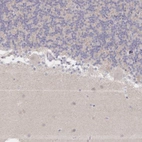

Immunohistochemical staining of human liver shows strong cytoplasmic positivity in hepatocytes.